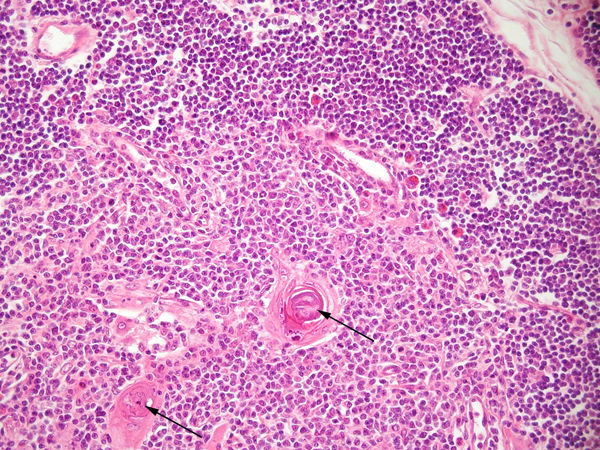

Question 3

Question

Identifiez les structures pointées ainsi que l'organe dans lequel on se trouve (en h à g). (milieu haut = petites structures rondes)

Image:

Thymus Fort Grossissement (image/jpeg)

Answer

thymus

corpuscule de Hassal

lymphocytes

cellules épithéliales